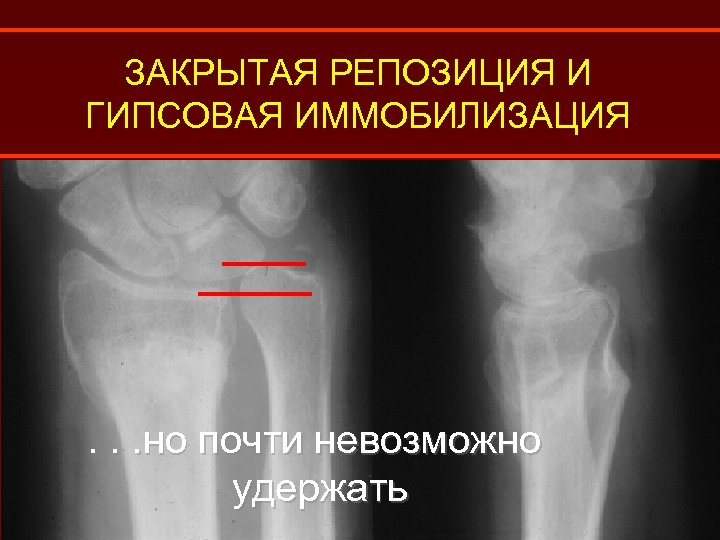

ЗАКРЫТАЯ РЕПОЗИЦИЯ И ГИПСОВАЯ ИММОБИЛИЗАЦИЯ

ЗАКРЫТАЯ РЕПОЗИЦИЯ И ГИПСОВАЯ ИММОБИЛИЗАЦИЯ Легко достичь репозиции. . .

ЗАКРЫТАЯ РЕПОЗИЦИЯ И ГИПСОВАЯ ИММОБИЛИЗАЦИЯ . . . но почти невозможно удержать